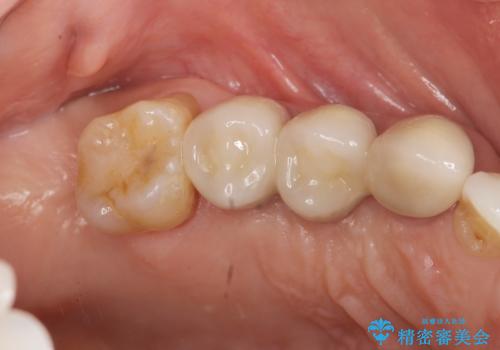

連結補綴について

特定の歯に強く力がかかりまた歯周病により臨床歯根が短くなっているような場合、歯の動揺を抑えるため連結補綴が検討されます。

歯の動揺が続くとより周囲の骨を失い最終的には歯を喪失してしまう可能性が高くなってしまうためです。

今回連結補綴を行うにあたり、歯周病の問題を解決するために再生療法・歯周ポケット除去手術を、またより歯の神経を保存し力に対抗できる環境を整えるために小矯正を行い精度の高いメタルボンドクラウンを製作することができました。